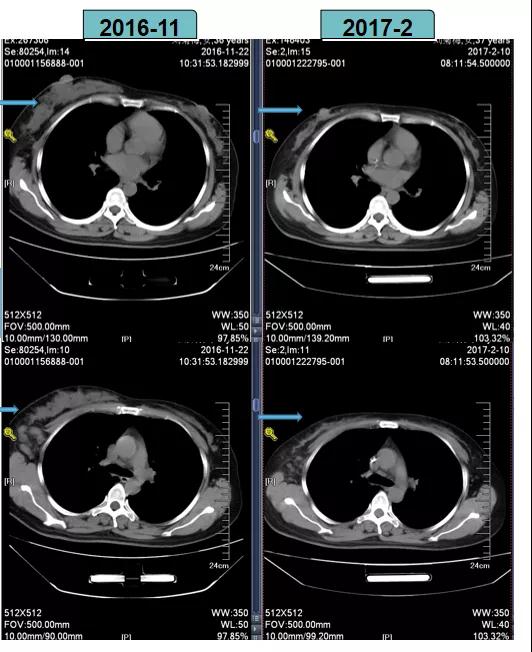

根据当时CSCO BC指南推荐的HER2阳性乳腺癌新辅助治疗策略,2016-11-29至2017-1-16给予TCbH方案进行新辅助化疗,后疗效评估为PR。

TCbH方案进行新辅助化疗后,患者疗效评估为PR

2017-2-10全麻下行右乳癌改良根治术。

术后病理(B201703357):病灶体积2cm×2cm×2.8cm,“右侧”乳腺非特殊型浸润性导管癌Ⅲ级,“右侧”腋窝淋巴结(18/18个)有癌转移。

免疫组化:ER(-),PR(-),HER2(3+),Ki-67(+40%)

术后诊断:右乳浸润性导管癌(ypT2N3aM0,IIIC期)。